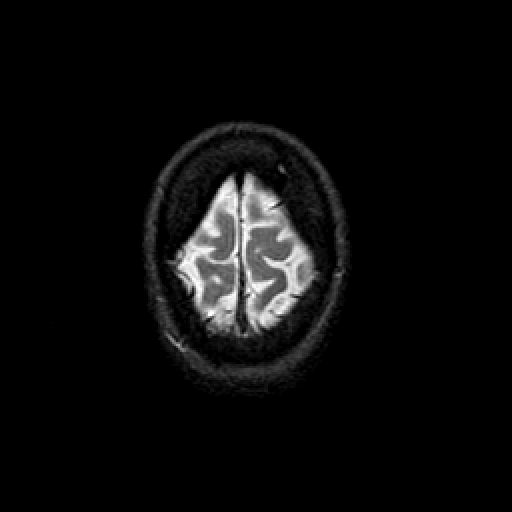

T2-weighted structural MR: Slice 48

Slice 48